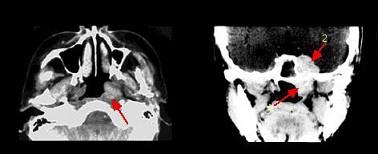

哪项不符合腺样囊性癌的肿瘤(如组图)生物学行为 ( )

哪项不符合腺样囊性癌的肿瘤(如组图)生物学行为 ( )![]()

A肿瘤易沿神经生长

B区域淋巴结转移率高

C侵袭性极强

D血行转移率高

E常出现神经症状